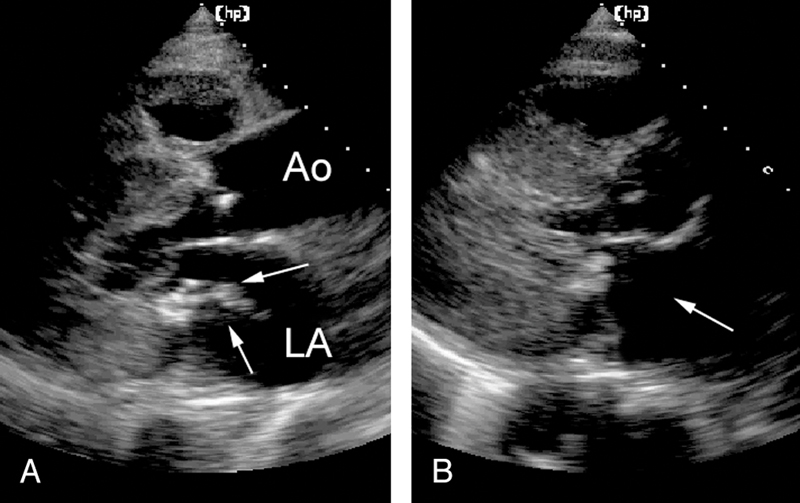

فحوصات تشخيصية لبعض امراض القلب والشرايين التاجية